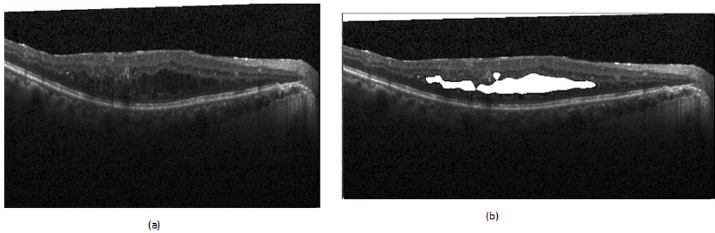

d) Volumetric Estimation: The volumetric estimation algorithm aimed to calculate the overall fluid volume content in a scan. This figure will be an additional quantitative measure for the medical professional. The automated estimation was achieved by running the deep learning algorithm over each individual 2D OCT scan, subsequently stacking these results together using the scanning distance to compile a representation of the data in a 3D space. Individual segmented fluid pockets which are the output of our proposed network converted to binary maps which used to calculate all of the connected components as each of these components was a potential candidate to be a region of fluid; see (Figure 2). The area of each of these potential candidates was calculated utilizing the green formula [17]. These calculated areas were used to filter the potential candidates through the application of a minimum area threshold to remove potential erroneous estimations that could be attributed to noise.

Figure 2: Examples of fluid segmentation performed by the network.

(a) Original Image

(b) Fluid Segmentation.